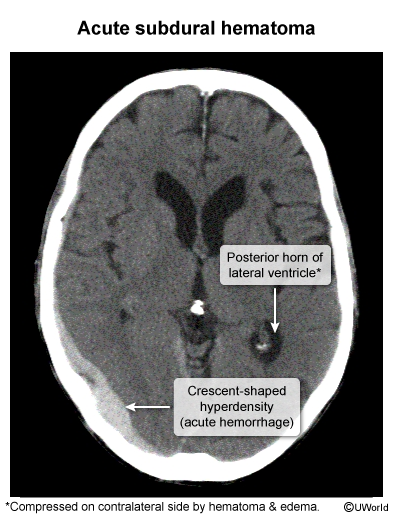

hx hip fracture, unsteadiness, now with progressive confusion, generalized weakness for several days

acute subdural hematoma caused by tearing of the bridging veins